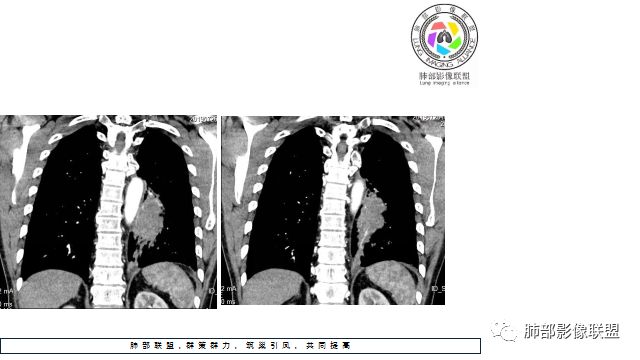

1.左下肺门区巨大肿块,支气管显示不清,轻度阻塞性炎症,没有明显肺不张,提示管腔受压狭窄可能性大于堵塞,这较少见于鳞癌。

2.病灶边缘光滑,未见明显分叶、毛刺,未见明显强化,这符合腺癌影像学特点,却符合神经内分泌癌表现。

3.病灶内密度均匀,轻到中度均匀强化,大病灶未见明显液化坏死区及空洞,不符合鳞癌而符合小细胞肺癌特点。

4.病灶内有肺动脉走形,血管局部受压,未见破坏,病灶乏血供,呈血管包埋或血管造影征;侵袭性力强及破坏力弱、血管漂浮都符合SCLC,所以鳞癌的可能性也不大。

5.左肺门块影或淋巴结肿大,竭力挤兑肺门血管结构,呈冰冻肺门;有时候SCLC可以单独呈现冰冻肺门,而没有没有冰冻纵隔。